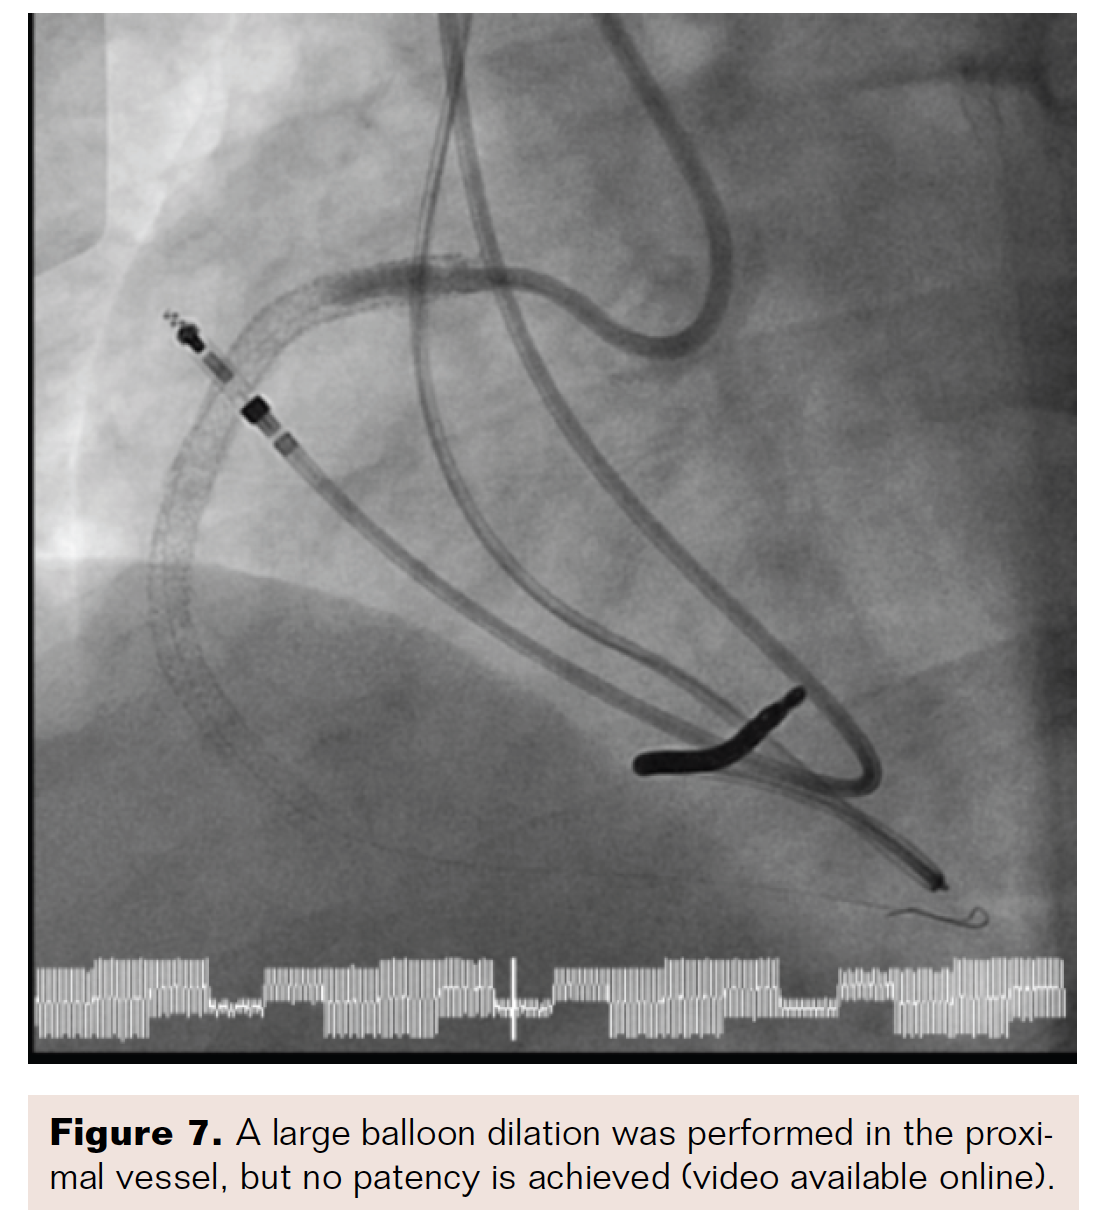

We entered from the right groin, and, using an 8 French right coronary artery Judkins guide catheter (Medtronic), passed the CrossLock device, as well as an 0.9 mm excimer coronary laser angioplasty (ECLA) catheter (Philips), and a Miracle 3 wire (Asahi Intecc). After entering the proximal third of the chronic total occlusion (CTO), we switched to a 7 French Amplatz guide catheter (Boston Scientific) and a Fielder XT guidewire (Asahi Intecc) (Figure 2). With the Fielder, we were able to travel approximately halfway across the vessel and address the lesion with the laser. We then passed the Whisper wire (Boston Scientific) into the posterior branch of the RCA, completely recanalizing the CTO (Figure 3). After recanalization, we performed balloon angioplasty with a 1.5 mm Somerset balloon (Terumo), followed by a 4 mm balloon in the proximal portion of the in-stent restenosis (Figures 4-5).